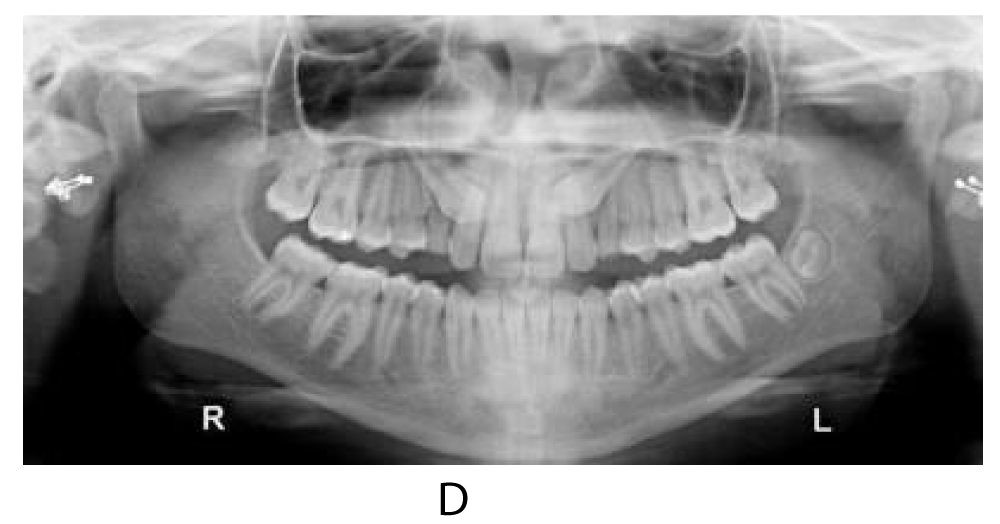

Panoramic radiographs showed the presence of two impacted canines. Considering the good morphology of the teeth, the position and the absence of ankylosis, in agreement with the oral surgeon the surgical orthodontic disimpaction was decided (Figure 1d).